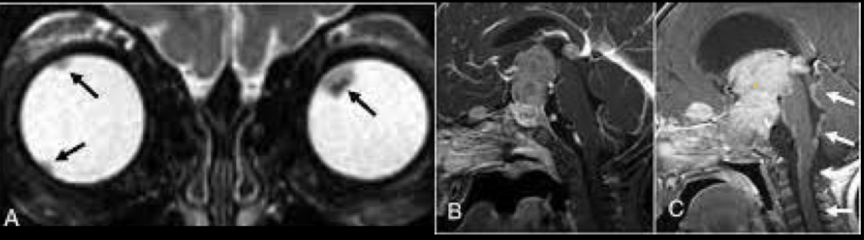

22

¿de qué enfermedad nos habla la siguiente imagen?

A

Retinoblastoma trilateral

24

¿de qué enfermedad nos hablan las siguientes imagenes?

Retinoblastoma cuadrilateral